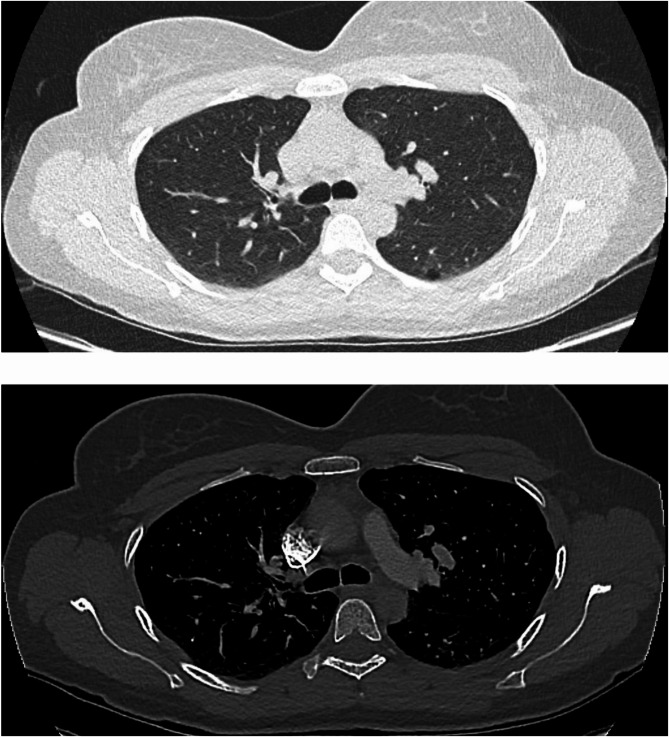

Case presentation: A 31-year-old woman developed respiratory failure 24 h after radiological embolization of pelvic varices. Glue embolization was detected during the intervention and was confirmed on a chest CT scan showing multiple bilateral hyperdense elements up to sub-pleural regions. The patient developed respiratory symptoms 24 h after the procedure, progressively worsening with oxygen requirement up to 6 L/min. A follow-up chest CT angiography showed a thrombotic pulmonary embolism. Treatments included curative anticoagulation, antibiotherapy, corticosteroids, and oxygen, leading to improvement after 10 days of treatment.